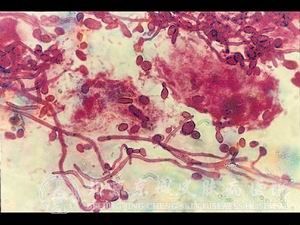

北京京城皮肤医院指出,念珠菌性支气管炎是皮肤病中的一种常见的疾病。由于念珠菌性支气管炎发病时期不同, 念珠菌性支气管炎症状表现都是基本不同的。因此,很多念珠菌性支气管炎病人都不是非常了解念珠菌性支气管炎到底是一种什么样的疾病。为了帮助广大患者更加了解念珠菌性支气管炎,北京京城皮肤医院将为您详细介绍念珠菌性支气管炎是什么。

北京京城皮肤医院指出:念珠菌性支气管炎的症状主要表现在咳嗽,痰属于粘液性胶状,通过实验可以查出致病菌。如果累及到肺部,会有胸痛,高烧甚至会引起死亡。